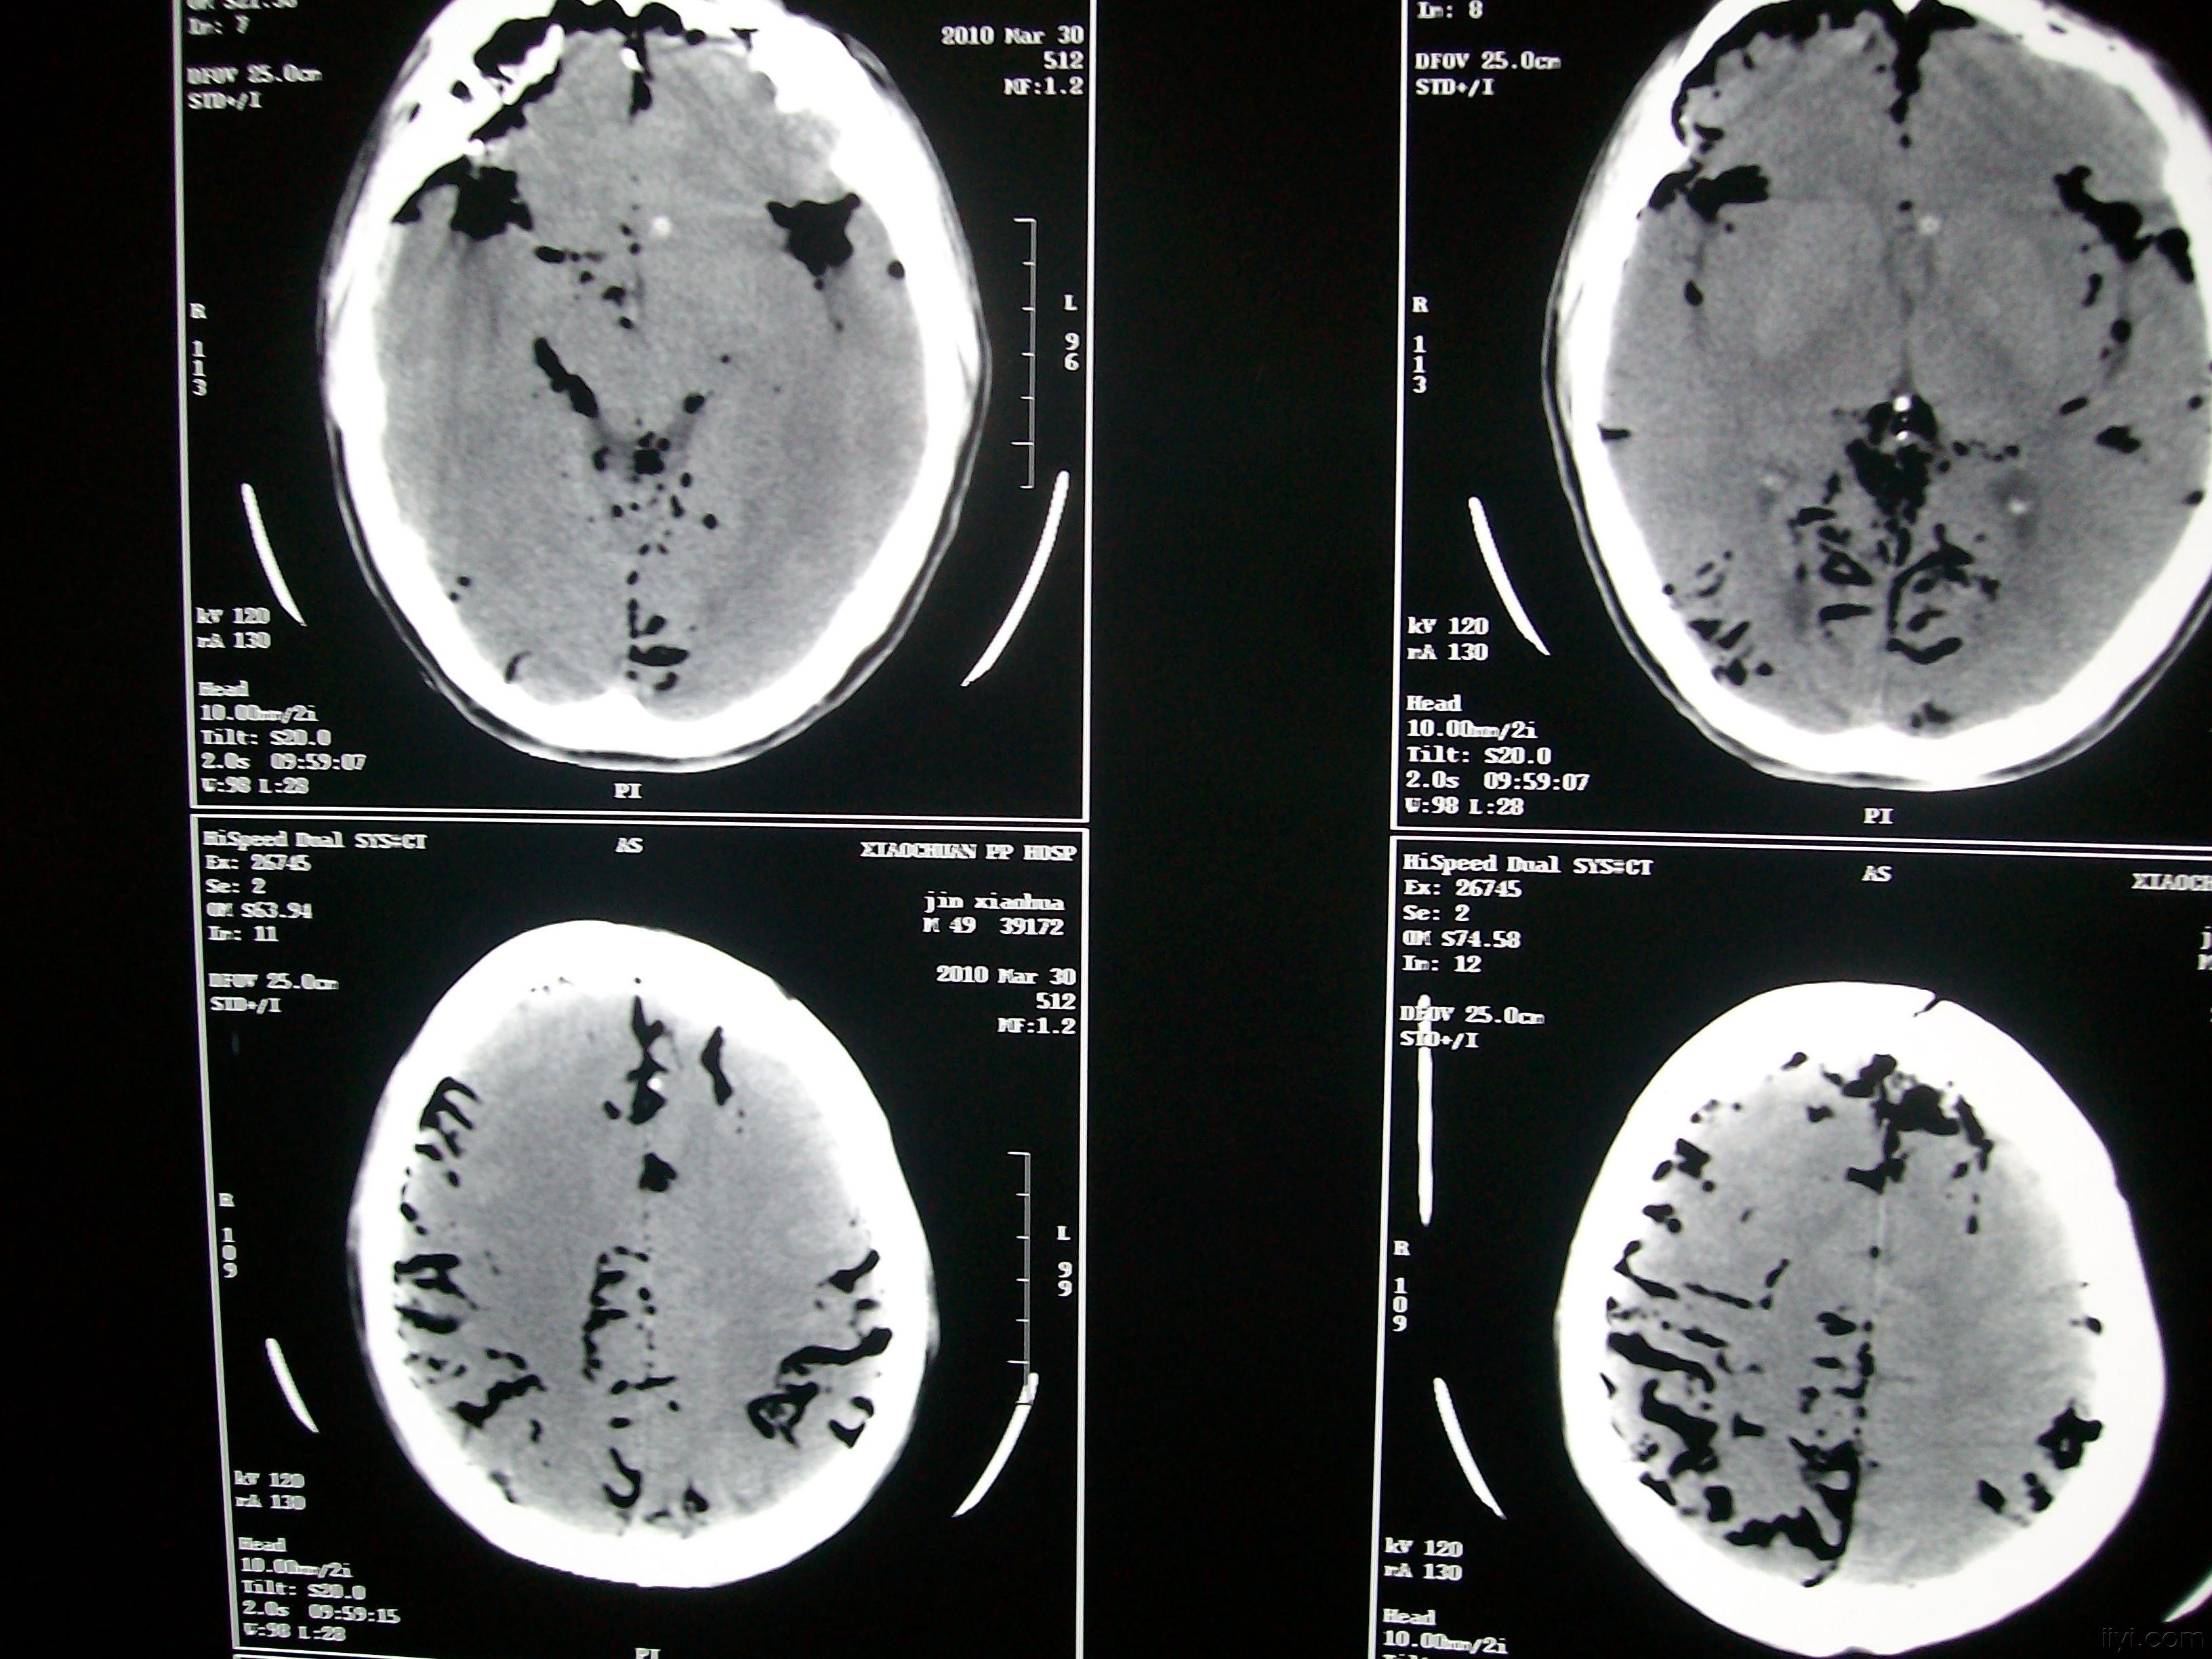

脑外伤导致的气颅

外伤--颅骨骨折并气颅 - 金叶子 - 耶子 河池市人民医院医学影像休闲